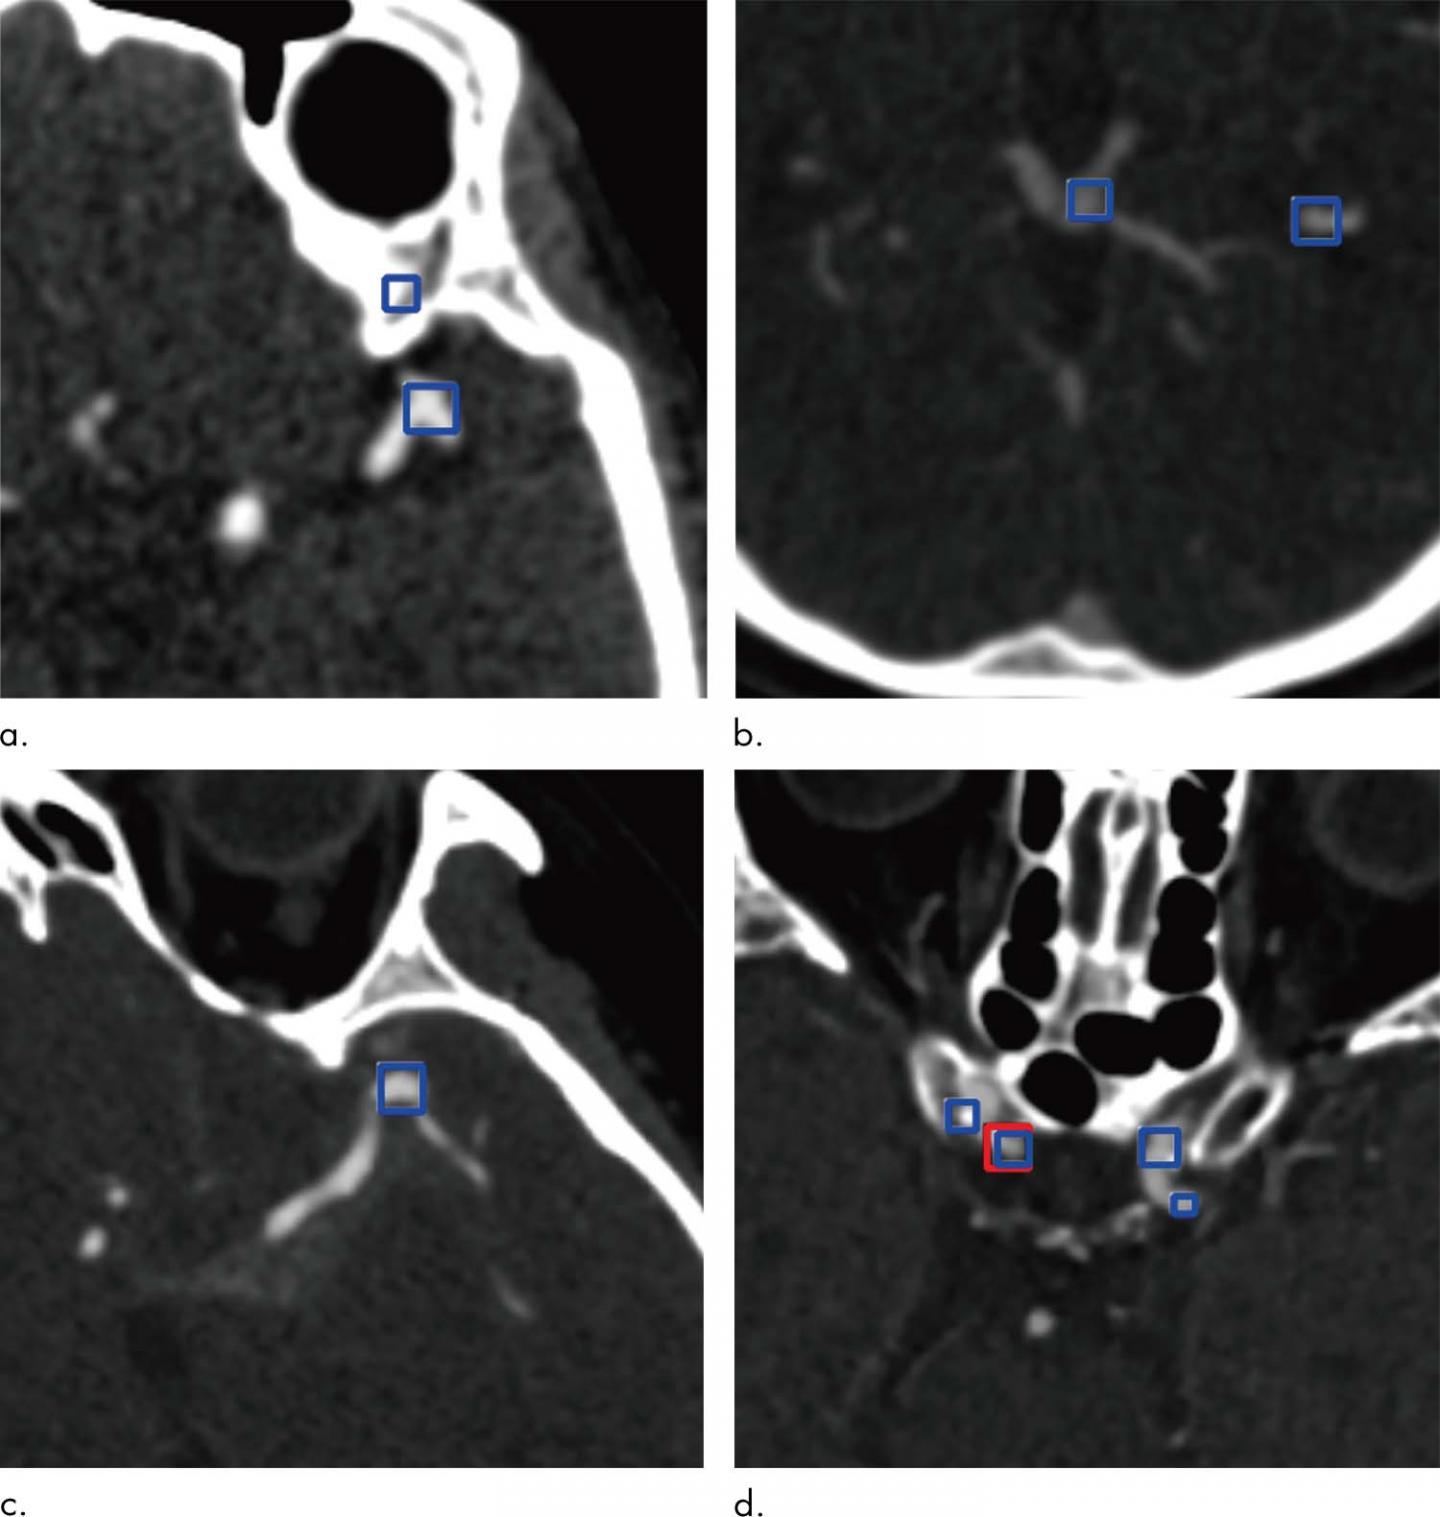

Images show examples of false-positive aneurysms, including (a) bony structures and vessel bifurcation, (b) veins, (c) vessel curvatures, and (d) calcified plaques. Red box (d) indicates aneurysms annotated by radiologists, and the blue boxes indicate aneurysm candidates provided by the algorithm. Images courtesy of the Radiological Society of North America

The system has some limitations, Long noted. It can miss very small aneurysms or aneurysms located close to similar density structures like bones. It also suffers from false positive results, meaning that it mistakenly identifies structures similar to aneurysms as aneurysms, which necessitates careful revision of the system suggestions by human readers.